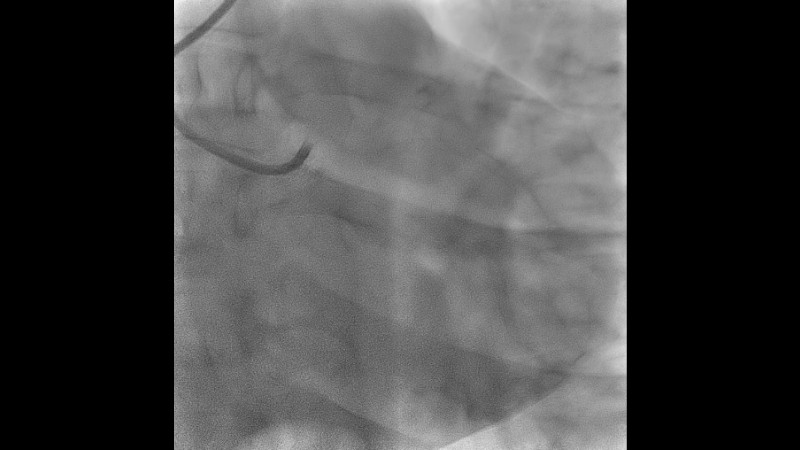

Explore the management of heavily calcified LAD lesions in this PCRGulf-GIM 2025 session. Discover how OCT imaging guides lesion assessment, differentiates superficial from deep calcium, and informs the need for plaque modification. Learn when and how to use orbital atherectomy or intravascular lithotripsy, and follow the step-by-step stent implantation, optimisation, and final evaluation using both angiography and OCT.

- To learn about the role of OCT imaging in the management of complex calcified coronary artery lesions.

- To learn indications of calcium modification using orbital atherectomy or other modalities, based on findings on OCT images.

- To learn the optimization of DES expansion by OCT in a complex calcified lesion.